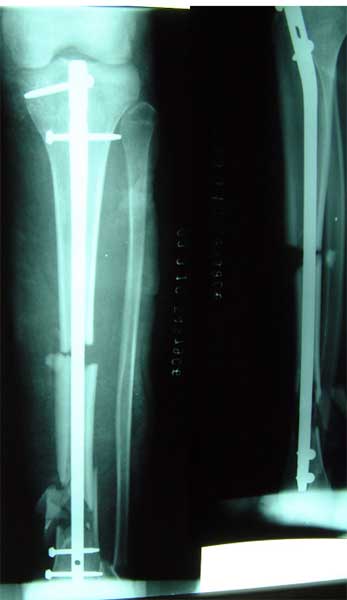

长骨干的力学特点是负重,两端为大关节,附着肌肉力量较大,应力突出。钢板内固定时广泛的软组织剥离,容易损伤血液循环和关节功能。 带锁髓内钉在骨组织和钉体之间提供较均匀的弹性应力分布,避免,抗旋转作用强于可屈髓内钉,不需外固定,对断端稳定性好,可早期功能锻炼。有优于钢板、外固定架和可屈髓钉的特点,已经成为治疗新鲜长骨干骨折的有效方法 。 但在长骨干骺端骨折、骨不连时,由于锁钉距离主钉孔较远,约在1.5-5.5厘米范围内,锁定骨折端有困难。 ZIMMER公司新型的带锁髓内钉可用于治疗长骨干骺端骨折、骨不连。由于锁钉距离主钉孔较近,约在0.5-3.5厘米范围内,可以满意锁定长骨干骺端骨折、骨不连。

胫骨中段、远端多段骨折,如果采用钢板固定,切口会很大,剥离骨膜,严重影响血运。由于中段、远端多段骨折,外固定架也难于获得满意固定效果。

采用特殊的带锁髓内钉固定多段骨折,可以采用闭合穿针方法,即不切开骨折部位的软组织,不破坏血液循环,不用外固定,可以早期锻炼关节,关节功能好,骨折愈合快。